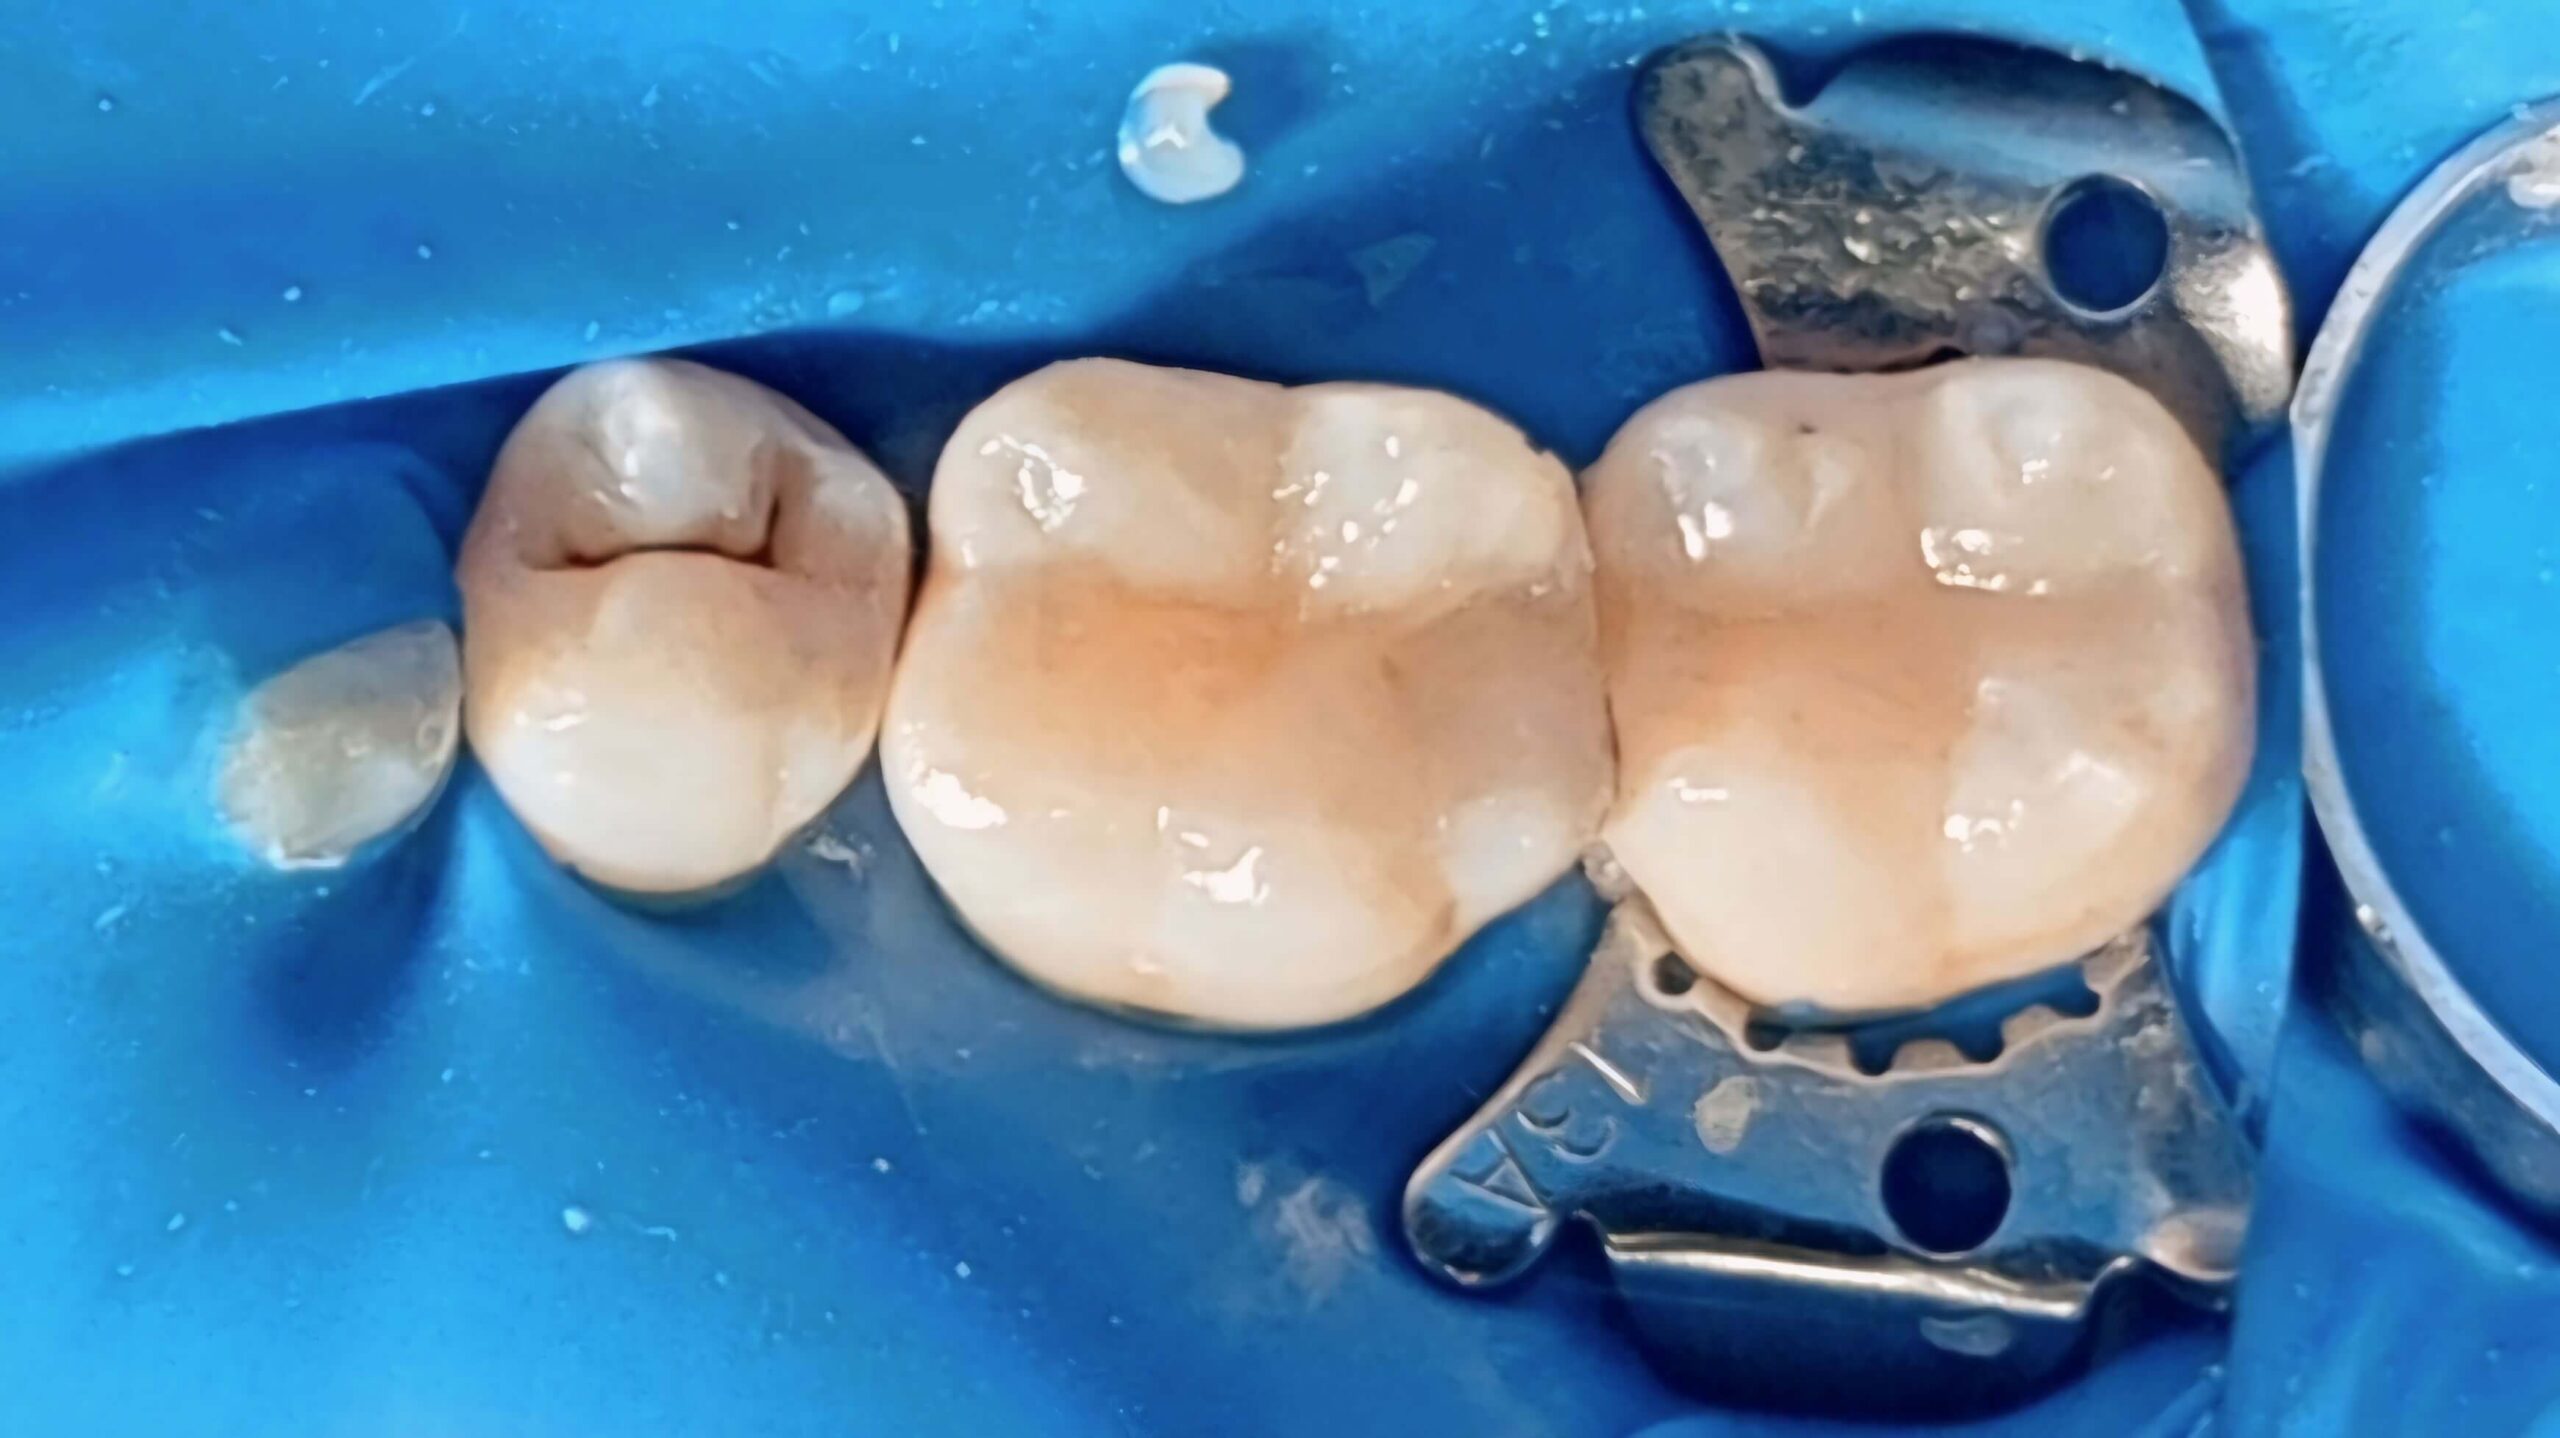

Художня реставрація зубів з використанням композитних матеріалів

Вихідна ситуація: дискомфорт під час жування та помітне пошкодження жувальної поверхні молярів. Оглянувши ротову порожнину пацієнта, ми виявили каріозну порожнину на жувальній поверхні зуба. Пролікувавши карієс ми запропонували естетичну реставрацію зуба з використанням композитних матеріалів. Як результат, пацієнт отримав відновлену поверхню зуба, яка не відрізняється за функціональністю та естетикою від природної.